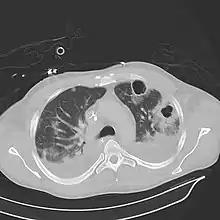

| Computed tomography (CT) scan of chest showing bilateral pneumonia with abscesses, effusions, and caverns. 37-year-old male. | |